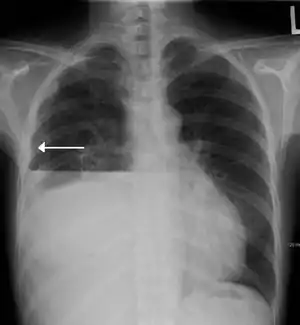

Hydropneumothorax

Hydropneumothorax is defined as the presence of both air and fluid within the pleural space.[1] An upright chest x-ray will show air fluid levels. The horizontal fluid level is usually well defined and extends across the whole length of hemithorax.

| A hydropneumothorax with white arrow point to the lung's pleura | |